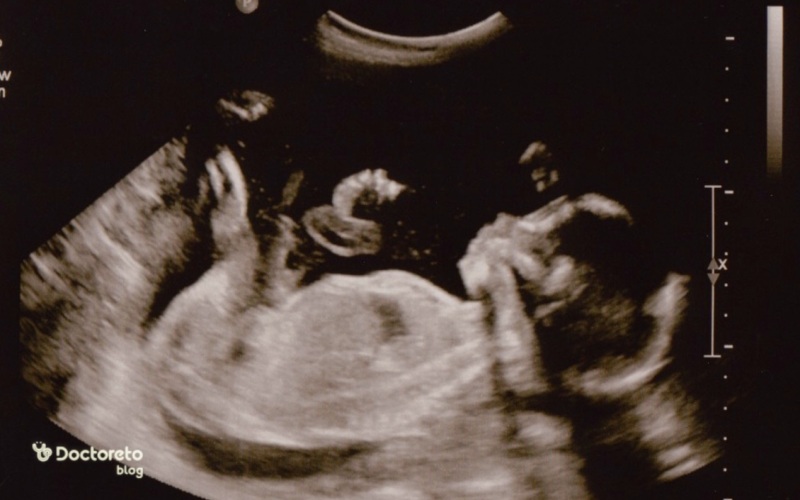

سونوگرافی در هفته ۲۲ بارداری

سونوگرافی سطح ۲ یا سونوگرافی سهماهه دوم بارداری در هفته ۱۸ تا ۲۲ بارداری انجام میشود. در این سونوگرافی آناتومی و میزان رشد جنین بررسی میشود. اگر چندقلو باردار هستید، آناتومی هر جنین جداگانه ارزیابی شده و میزان رشد بررسی خواهد شد.

در این سونوگرافی باید مغز، قلب، ستون فقرات، اجزای صورت، اندامهای شکمی و تناسلی و سایر اندامها بررسی شوند. ممکن است در حین سونوگرافی بتوانید لگد زدن جنین را ببینید.